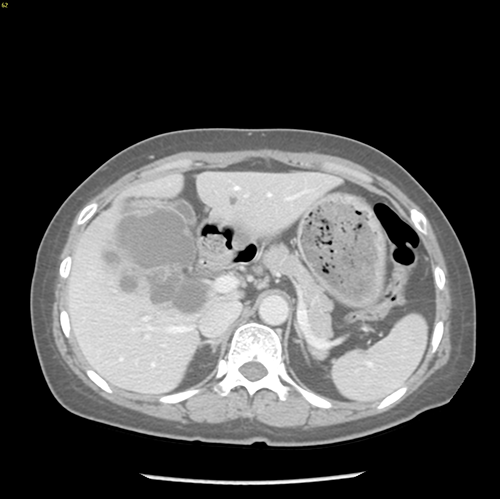

右肝胆管囊腺瘤----S5囊腺瘤切除、胆囊切除